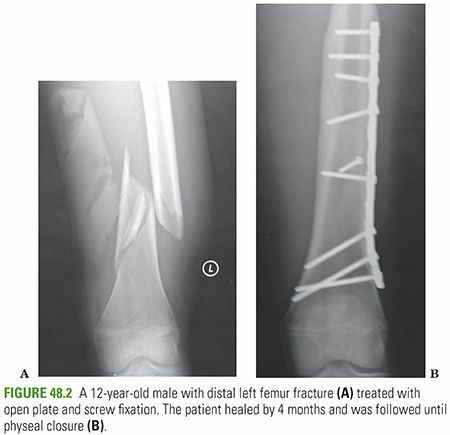

- This may be accomplished using a 3.5- or 4.5-mm compression plate, with or without interfragmentary compression of fragments; it is less desirable because of the long incision necessary, significant periosteal stripping, quadriceps scarring, frequent need for plate removal, and infection. (Fig. 48.2)

- Percutaneously placed, submuscular locking plates are useful for supracondylar, shaft, and subtrochanteric fractures in which intramedullary devices have limited fixation. Less soft tissue stripping needed, but infection and plate removal remain concerns.